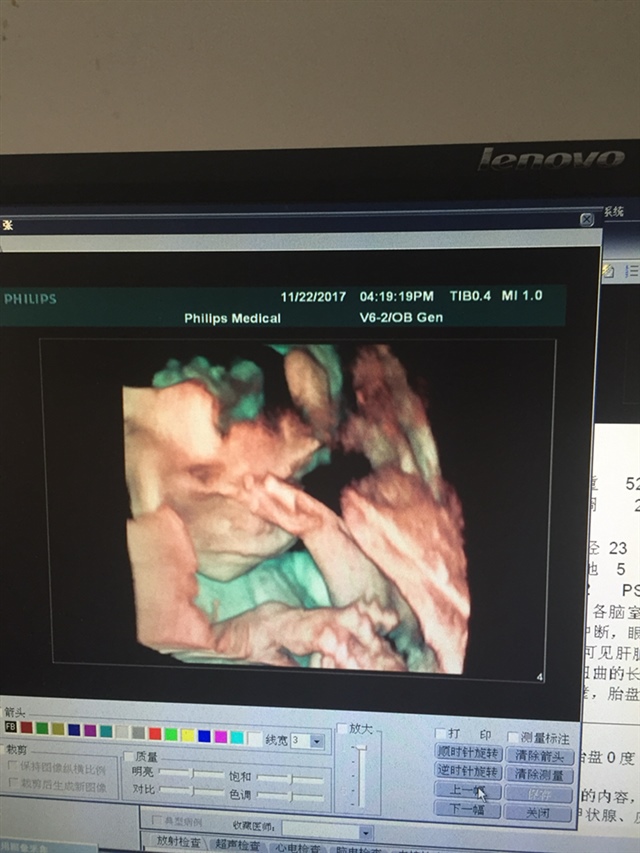

宝宝4个月3天

像你老公多点,在揉眼睛好可爱啊